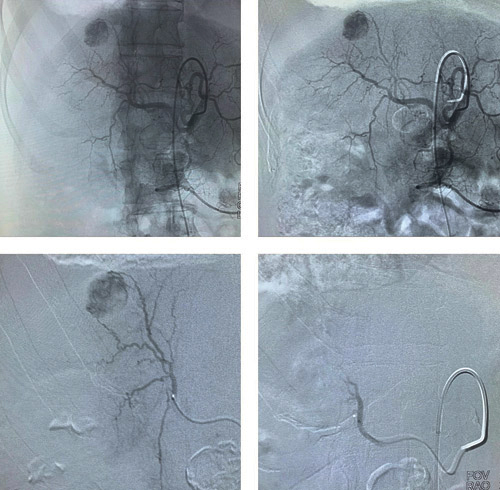

ذكر ذلك الأستاذ الدكتور سليمان الماجد المدير الطبي للمستشفى، والذي قال إن المريض قد تمت معاينته في عيادة الكبد حيث كان يتابع علاجه، وتم تحويله لعيادة الأشعة التداخلية، إذ إن حالته الصحية لم تكن تسمح بزراعة أو استئصال الكبد، حيث كان يعاني من أمراض مزمنة عدة، فقام الفريق الطبي بدراسة حالته على ضوء الفحوصات الطبية التي خضع لها خاصة الأشعة المقطعية، وخلص إلى ضرورة التدخل عبر القسطرة والأشعة التداخلية، وبعد اتخاذ الترتيبات اللازمة، أخضع المريض إلى إجراء طبي حديث تحت التخدير الموضعي، إذ تم إدخال القسطرة عبر فتحة لم يتجاوز طولها «3» مليمترات بالجلد، للوصول إلى شرايين الكبد، ومن ثم استخدام قساطر رفيعة تم إدخالها إلى الشريان المغذي للورم، ومن ثم حقن العلاج الكيماوي ومواد غالقة في الشريان المغذي للورم، وقد استغرق هذا الإجراء نحو ساعة، وقد تكللت العملية -ولله الحمد- بالنجاح التام، وغادر المريض المستشفى إلى منزله بحالة صحية جيدة، وستتم متابعة علاجه في عيادات الكبد والأورام والأشعة التداخلية.

وأضاف أ. د. الماجد أن هذه هي المرة التي يتم فيها استخدام هذا النمط من العلاج الكيماوي، موضحاً أنه يرتكز على حقن العلاج الكيماوي بشكل موضعي في الشريان المغذي للورم فقط، وبشكل دقيق جدًا عن طريق الأشعه التداخلية، وتابع قائلاً: تستخدم هذه الطريقة مع الحالات التي لا تناسبها زراعة أو استئصال الكبد، وهي تُعد من الإجراءات الطبية الحديثة لعلاج الأورام، وتتوفر فقط في المستشفيات والمراكز المتخصصة الكبيرة.